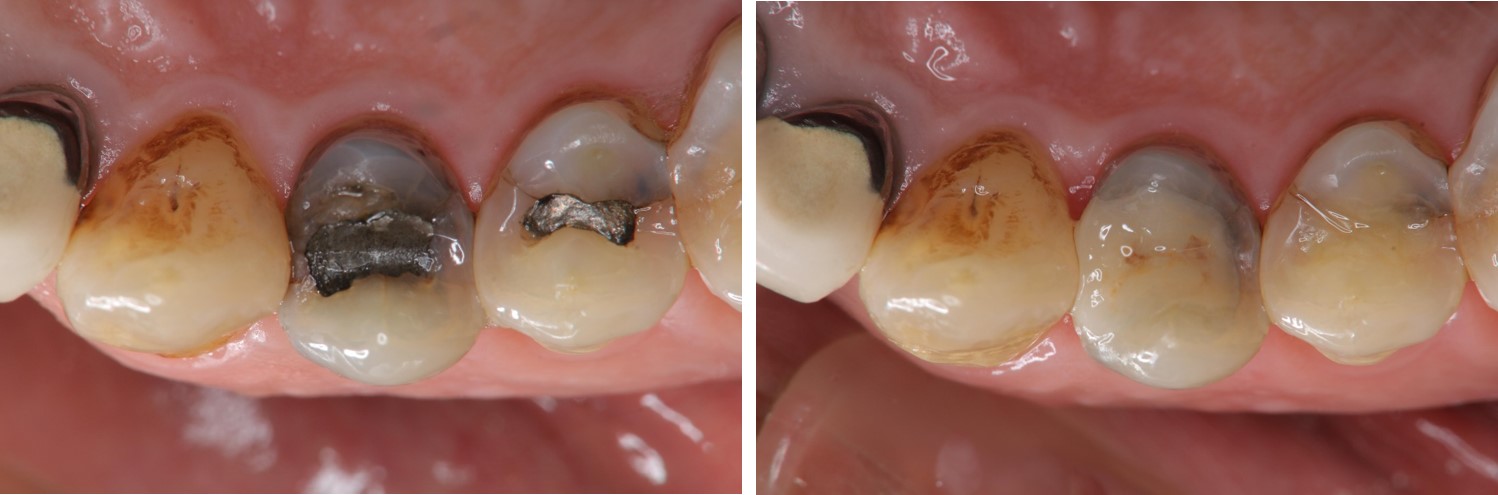

術前、術後比較